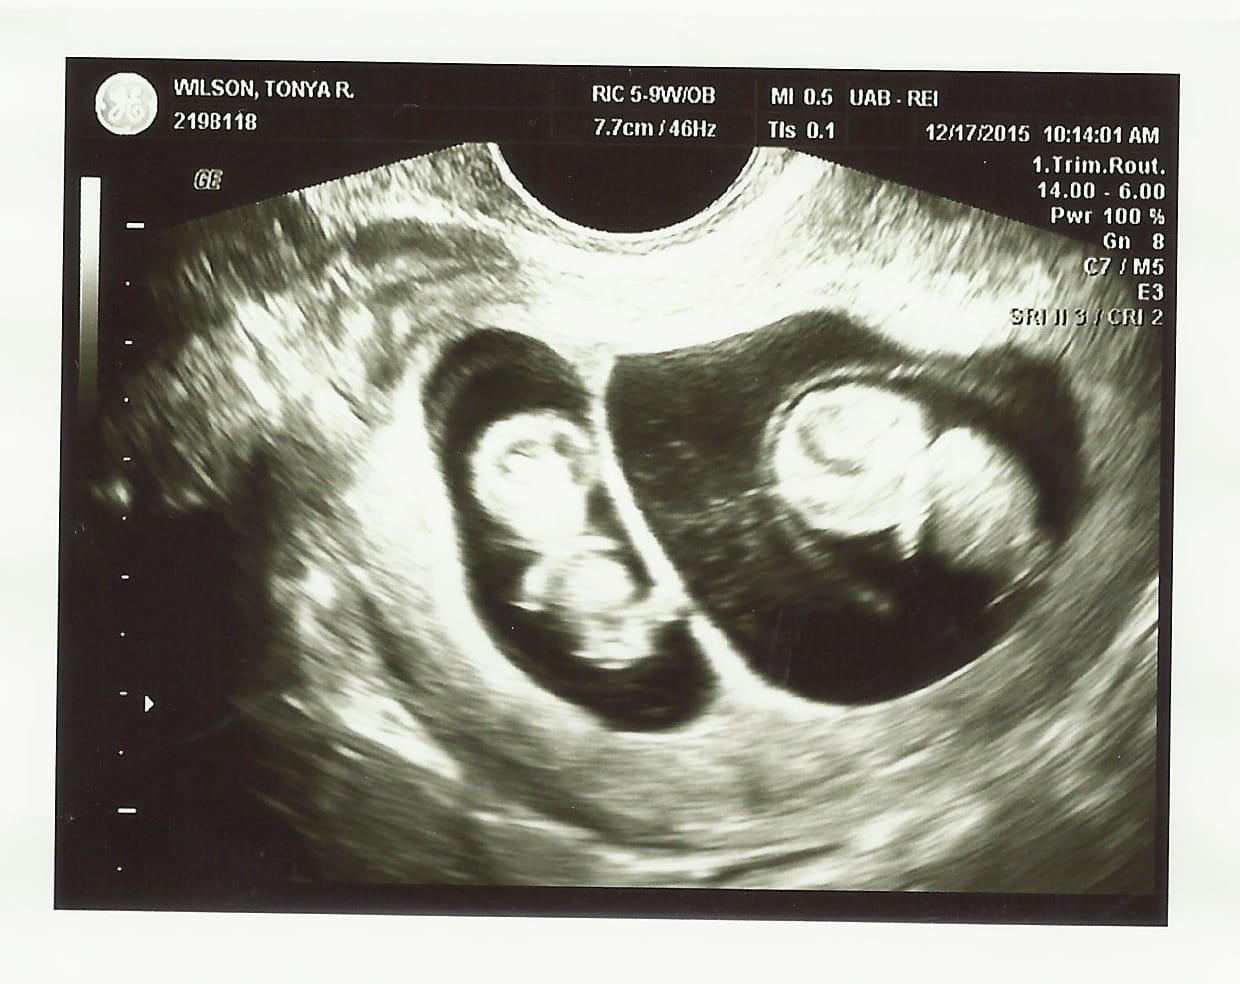

Ultrasound Photos of 9 Weeks Pregnant With Twins